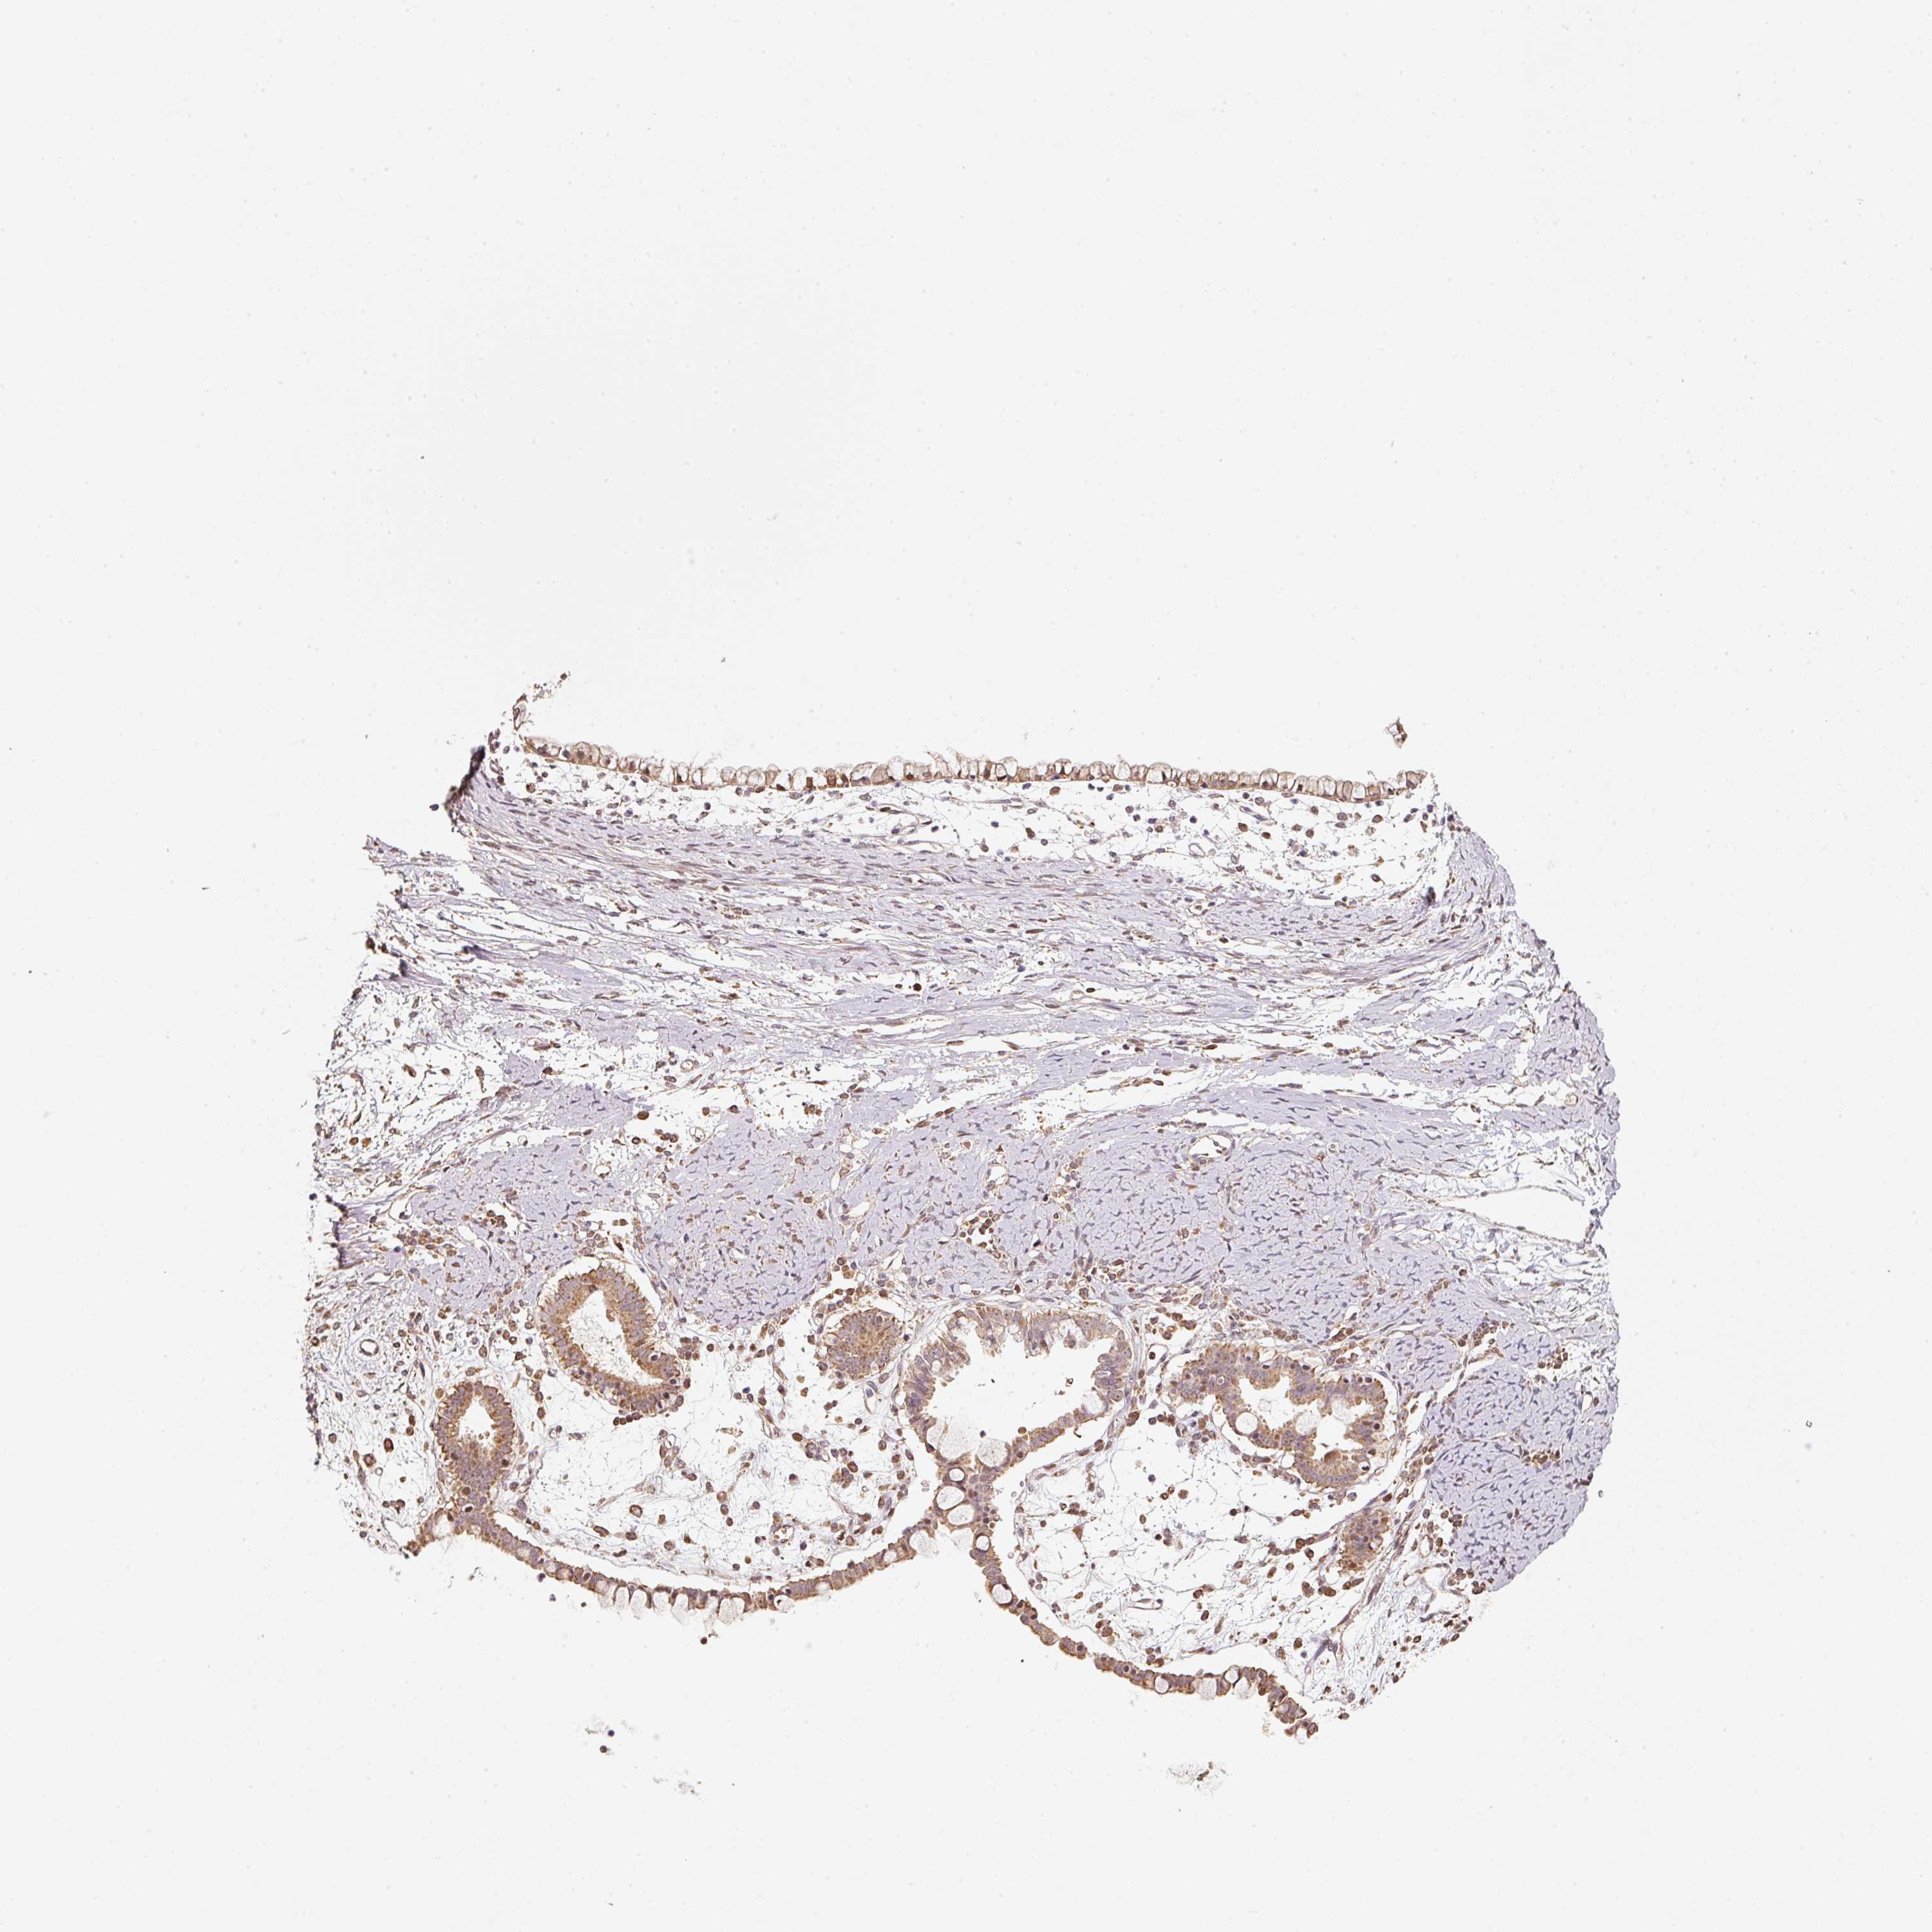

OVARIAN CANCER - Protein expressioni

A mouse-over function shows sample information and annotation data. Click on an image to view it in a full screen mode. Samples can be filtered based on level of antibody staining by selecting one or several of the following categories: high, medium, low and not detected. The assay and annotation is described here.

Note that samples used for immunohistochemistry by the Human Protein Atlas do not correspond to samples in the TCGA dataset.

Antibody stainingi

Antibody staining in the annotated cell types in the current human tissue is reported as not detected, low, medium, or high, based on conventional immunohistochemistry profiling in selected tissues. This score is based on the combination of the staining intensity and fraction of stained cells.

Each image is clickable and will lead to virtual microscopy that enables deeper exploration of all samples and also displays staining intensity scores, fraction scores and subcellular localization as well as patient and tissue information for each sample.

Antibody HPA054146

Cystadenocarcinoma, serous, NOS

Cystadenocarcinoma, mucinous, NOS

Adenocarcinoma, NOS

Carcinoma, endometroid